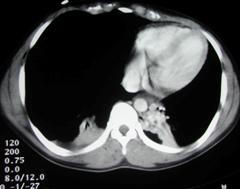

Pneumotorace sufocant bilateral Pneumotorace sufocant stang

Pneumotorace

sufocant stang Pneumotorace

sufocant drept Pneumotorace

sufocant drept

Imagine

CT Imagine CT